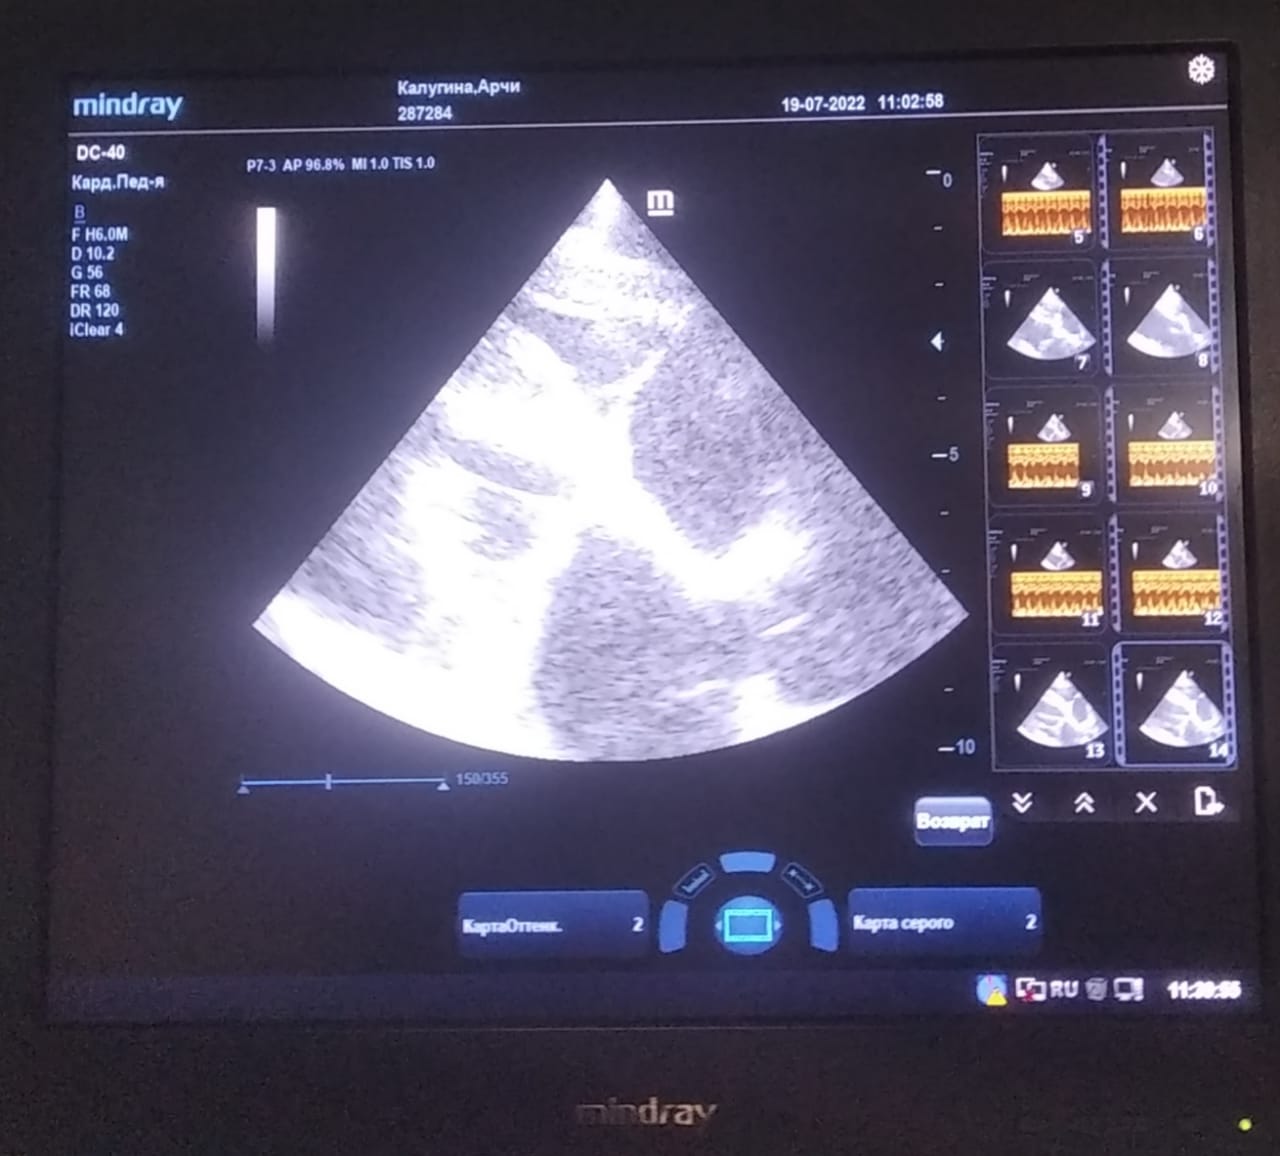

Анализы Арчи. Сердца и легких

Вложения

IMG-20220719-WA0100.jpg

IMG-20220719-WA0102.jpg

IMG-20220719-WA0104.jpg

IMG-20220719-WA0103.jpg

IMG-20220719-WA0105.jpg

Хорошо бы рентген легких и эхо сердца.